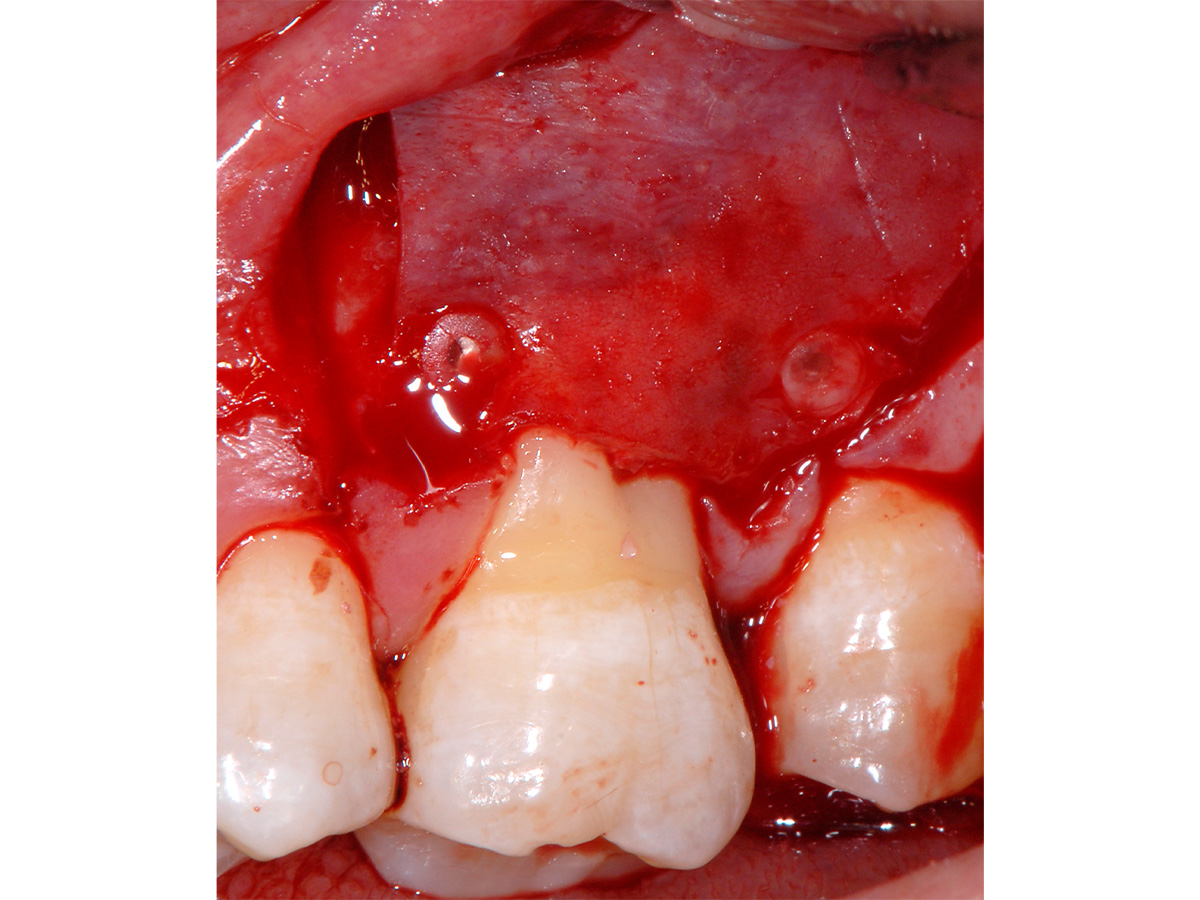

Abbildung 3

Mikrochirurgischer Zugang mit Schonung der interproximalen Bereiche. Vorbereitung dort durch Entepithelisierung zur späteren koronalen Verschiebung der bukkalen Lappenanteile.